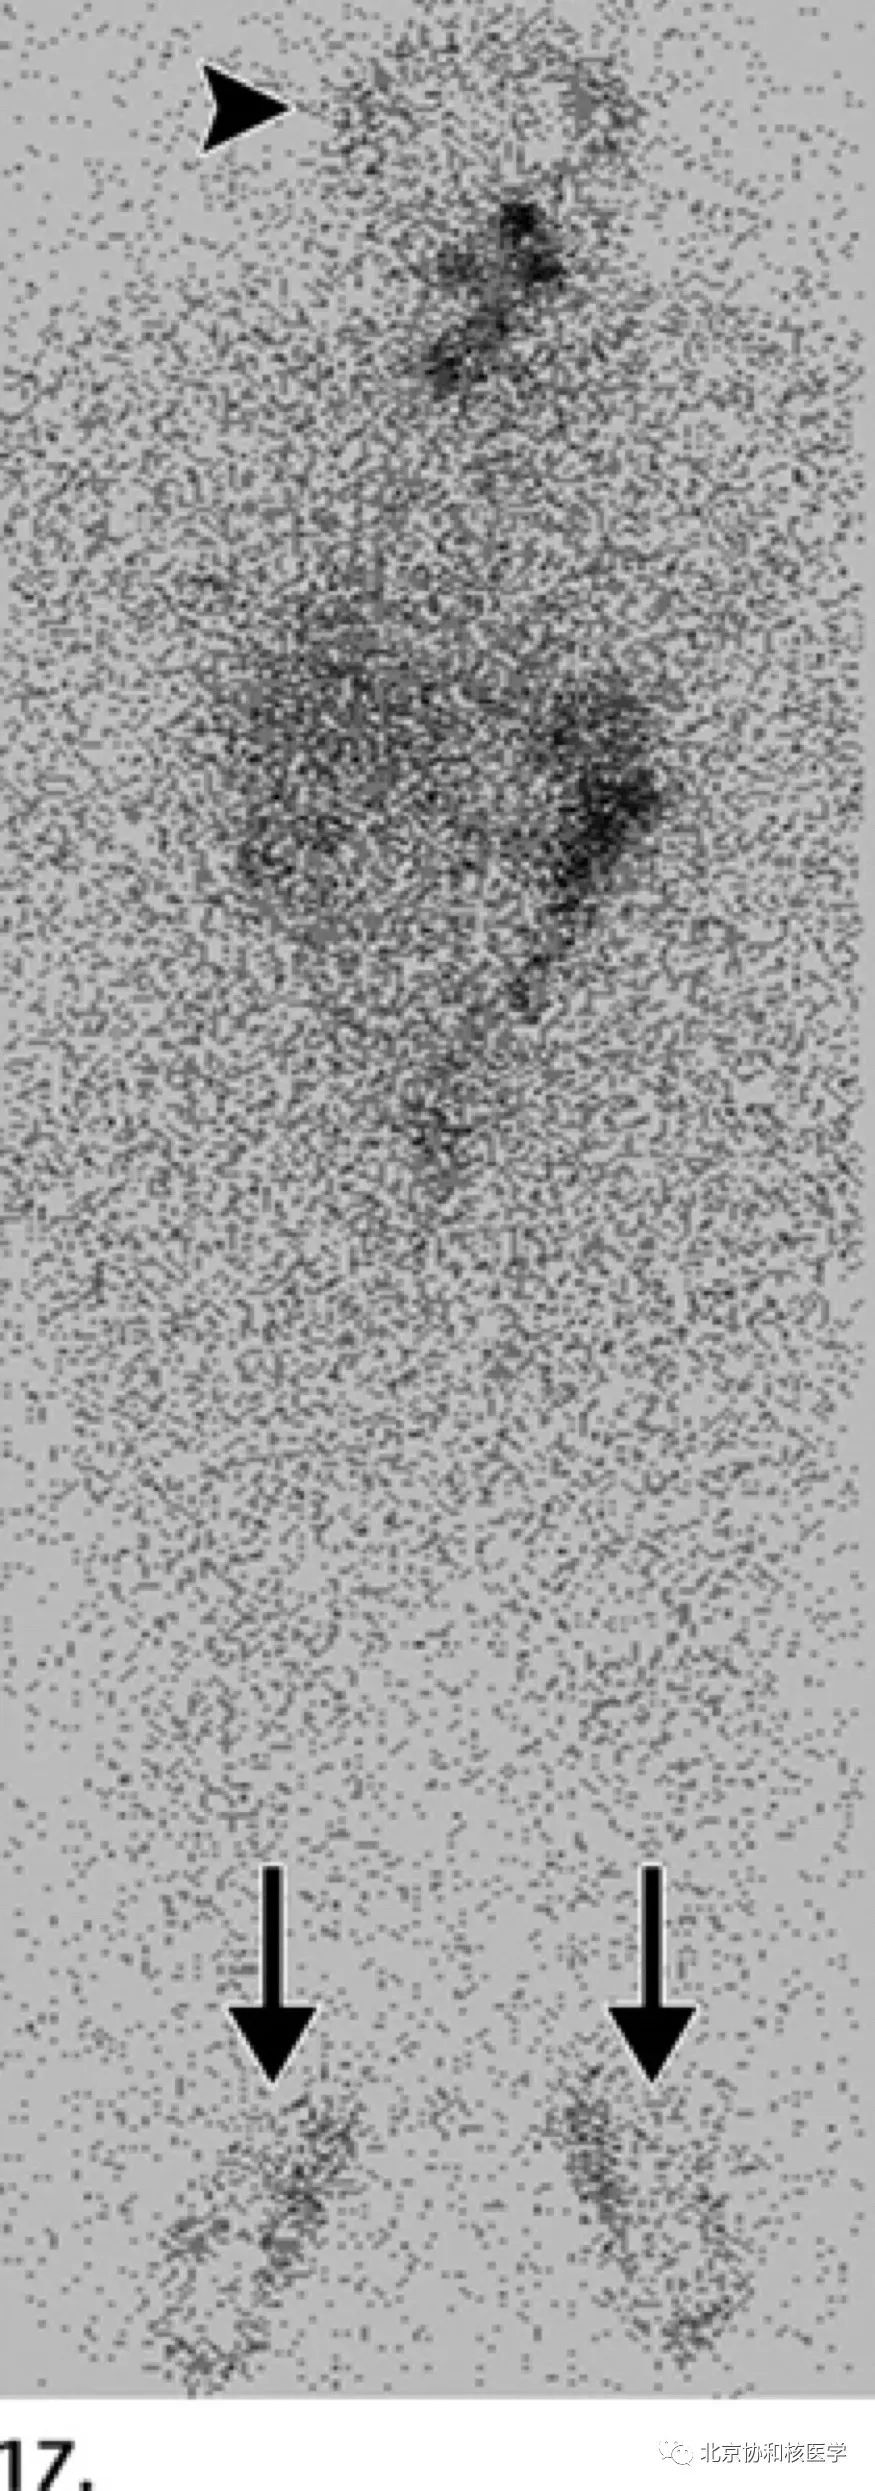

54岁女性,甲状腺乳头状癌甲状腺全切除术后,碘131治疗后碘扫见足周、头皮由于汗液中放射性碘的污染导致的异常摄取:

小腿外伤导致的碘131摄取: